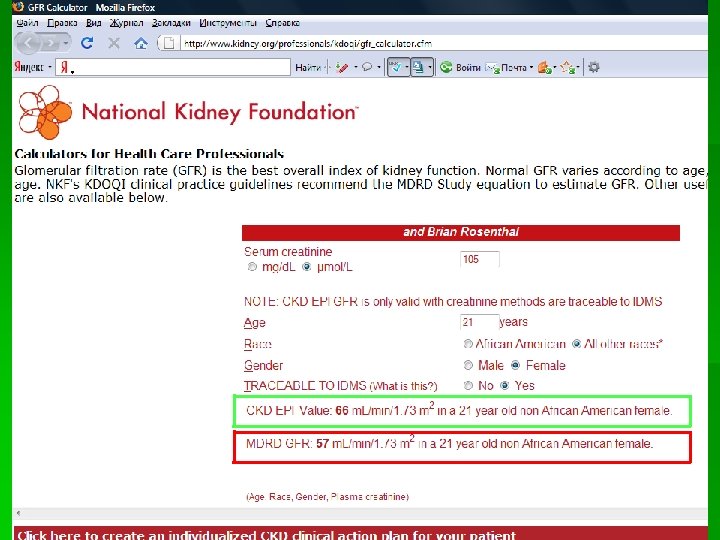

Формула CKD-EPI, модификация 2011 г. (мл/мин/1, 73 м 2) Раса Пол Креатинин сыворотки (Кр) Формула Белые Женский ≤ 0, 7 (≤ 62 мкмоль/л) 144 х. Кр/0, 7 -0, 329 х0, 993 Возраст Белые Женский >0, 7 (>62 мкмоль/л) 144 х. Кр/0, 7 -1, 209 х0, 993 Возраст Белые Мужской ≤ 0, 9 (≤ 80 мкмоль/л) 141 х. Кр/0, 9 -0, 411 х0, 993 Возраст Белые Мужской >0, 9 (>80 мкмоль/л) 141 х. Кр/0, 9 -1, 209 х0, 993 Возраст Азиаты Женский ≤ 0, 7 (≤ 62 мкмоль/л) 151 х. Кр/0, 7 -0, 329 х0, 993 Возраст Азиаты Женский >0, 7 (>62 мкмоль/л) 151 х. Кр/0, 7 -1, 209 х0, 993 Возраст Азиаты Мужской ≤ 0, 9 (≤ 80 мкмоль/л) 149 х. Кр/0, 9 -0, 411 х0, 993 Возраст Азиаты Мужской >0, 9 (>80 мкмоль/л) 149 х. Кр/0, 9 -1, 209 х0, 993 Возраст Примечание: не приведены формулы для негроидной расы, испаноамериканцев и индейцев. Для расчета СКФ по формуле CKD-EPI можно воспользоваться калькуляторами, представленными в интернете (http: //www. kidney. org/professionals/kdoqi/gfr_calculator. cfm, http: //nkdep. nih. gov/professionals/gfr_calculators/index. htm), специальными приложениями для мобильных устройств (Qx. MDCalculator), номограммами.